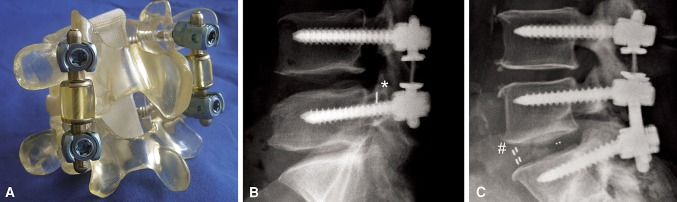

Fig. 1A–C.

Images illustrate the CD Horizon® Agile™ implant. (A) An SL configuration of the implant is shown mounted to a Sawbones® model. (B) A lateral radiograph shows the SL configuration in a patient after previously performed sequestrectomy, indicated by a clip (*). (C) A lateral radiograph shows a patient with the TO configuration of the implant in combination with single-level PLIF (# indicates markers in the PEEK cages).